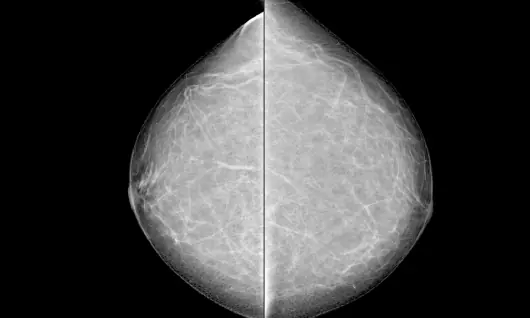

Tejido mamario

¿Puede una mamografía ser igual de eficaz en todas las pacientes? ¿Qué sucede cuando el tejido mamario denso dificulta la visualización de lesiones tempranas? Hoy, los equipos de mamografía han evolucionado para responder a este reto clínico mediante detectores digitales más sensibles, procesamiento avanzado de imagen y tecnologías como la tomosíntesis.

• Puede dificultar la detección temprana de lesiones: el tejido mamario denso aparece blanco en la mamografía, al igual que muchas lesiones tumorales. Esta similitud en la apariencia radiográfica puede ocultar hallazgos pequeños o incipientes, retrasando su identificación en estudios convencionales.

• Se desempeña en mamas densas: diversas fuentes clínicas señalan que la mamografía digital puede ofrecer mejor desempeño en mujeres con tejido mamario denso, ya que el procesamiento electrónico permite una visualización más detallada de áreas complejas en comparación con la película tradicional.